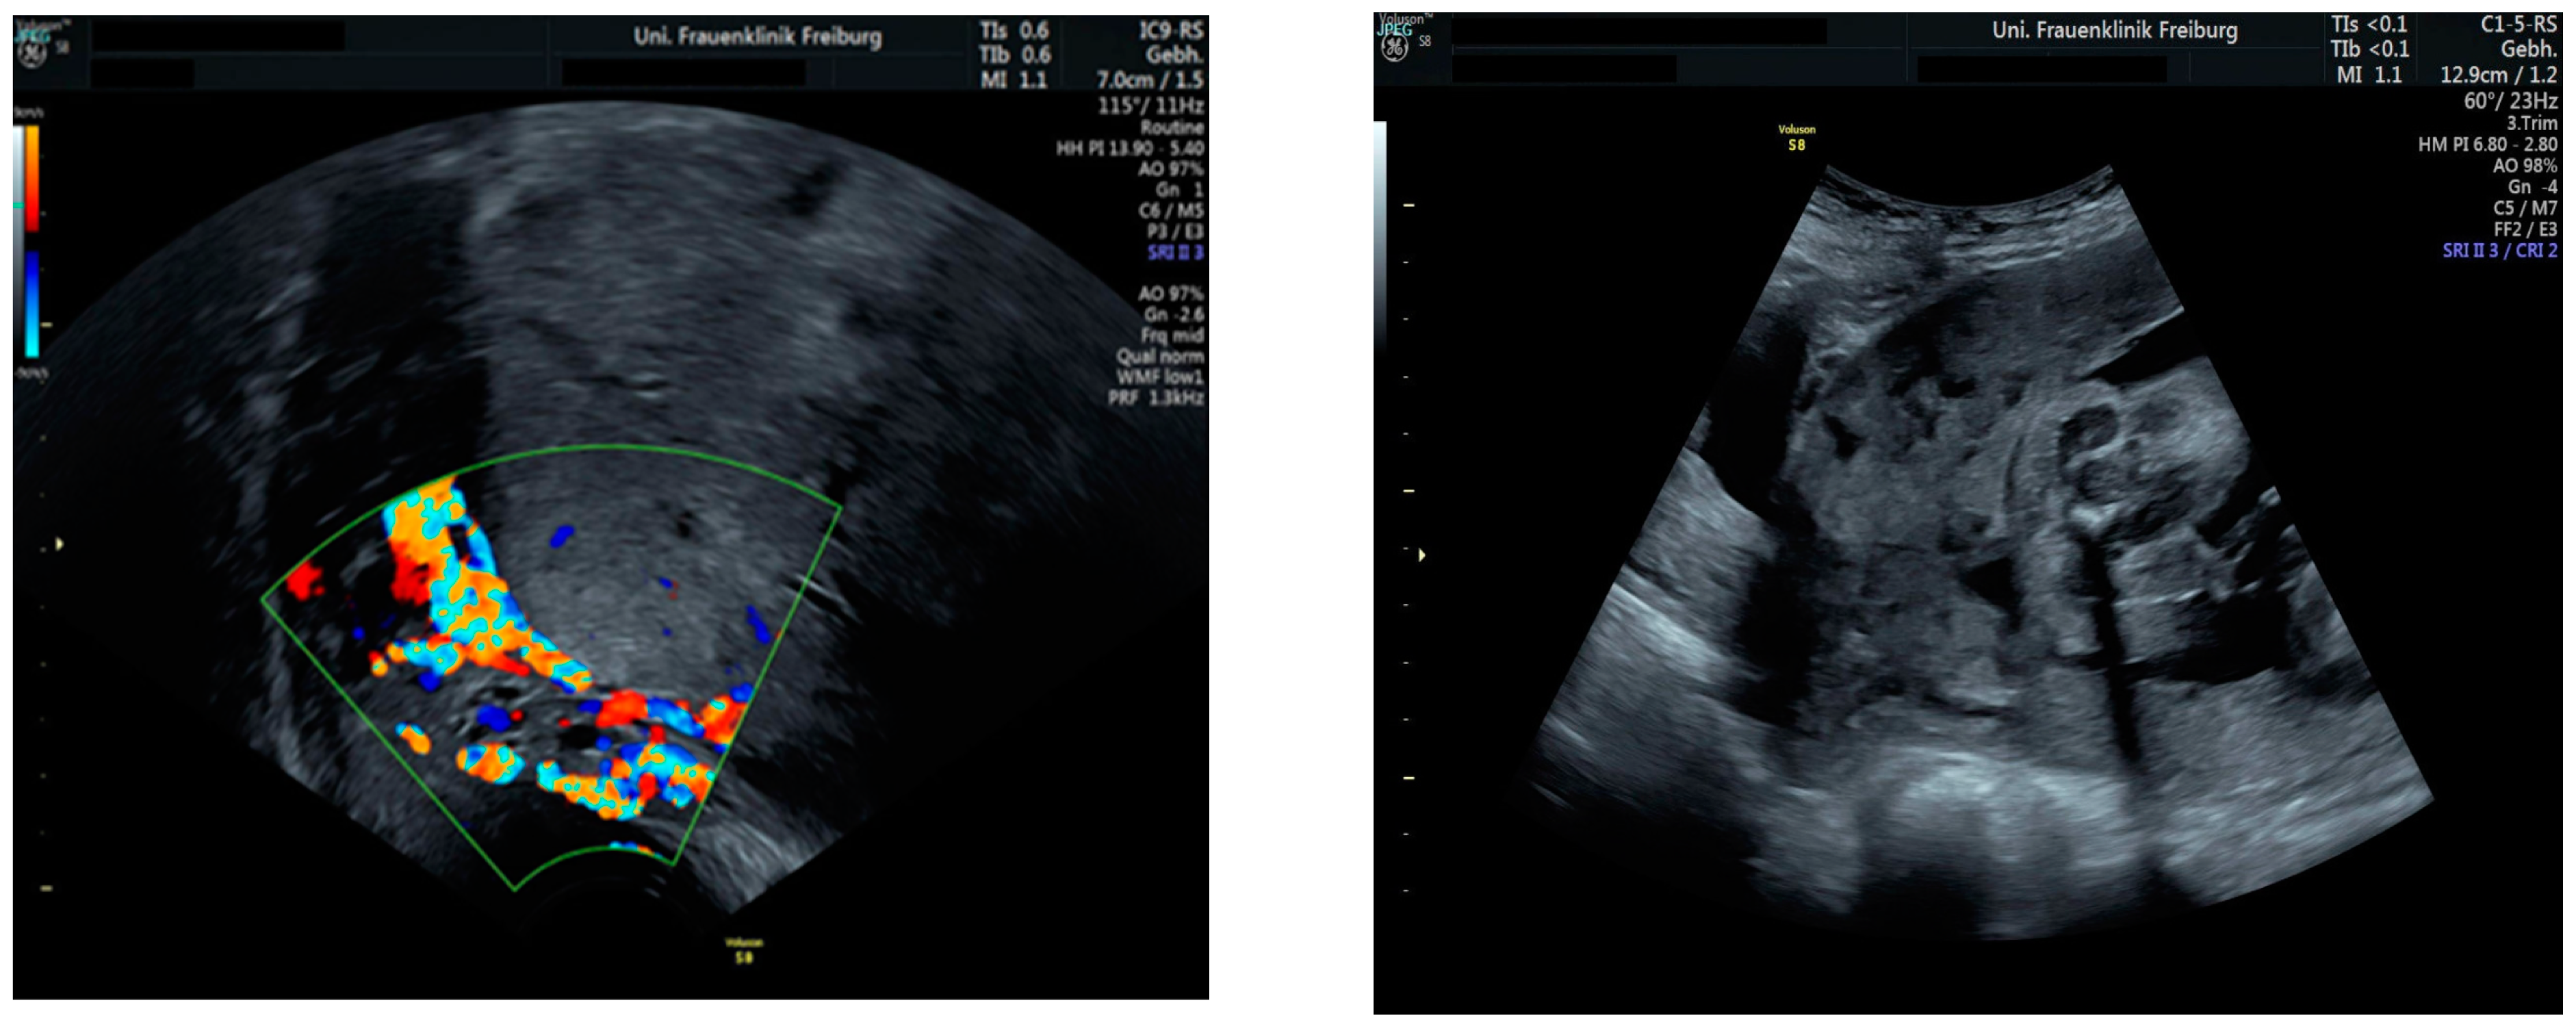

Sonographic findings (Figure 2):

Figure 2.

Irregular and large lacunae: Sonographic imaging reveals irregularly shaped and enlarged lacunae within the placenta. Hypervascularity: Increased vascularity is observed within the placenta, indicating abnormal blood flow. Turbulent flow in lacunae: Doppler imaging demonstrates turbulent blood flow within the lacunae, suggestive of abnormal vascularization. Changes in diameter: Variations in the diameter of lacunae may be noted on sonographic examination, reflecting the dynamic nature of placental vascularization in PAS.